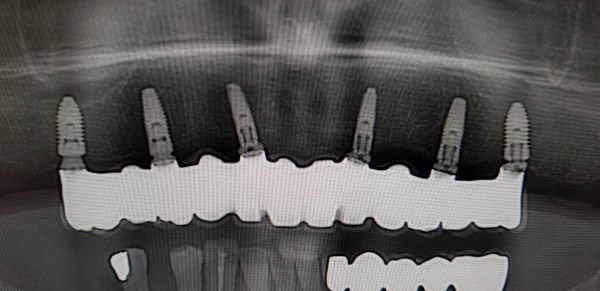

Felső fogatlan állcsont korszerű ellátása: felső teljes fogatlanság kezelése 6 implantátumon rögzített fix híddal. Multi unit tengelykorrekciós fejek, csavarosan rögzített híd.

Implantátum: Nobel Biocare.

Hídpótlás anyaga: cirkónium vázra égetett porcelán.

A választott fogszín: A1.

A protetikai munka elkészülésének ideje: 8 munkanap.